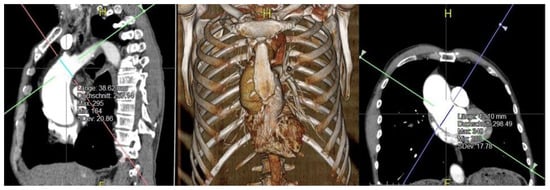

In order to identify a potential reference value for the application of our institutional method regarding suitable aneurysmatic diameter at the different levels of the ascending aorta we retrospectively performed biplanar measurement. CT angiography scans were reconstructed automatically using Aquarius iNtuition (TeraRecon Inc., Foster City, CA, USA).

Based on ECG-gated computed tomography angiograms (CTAs) biplanar measurements at the level of the sinotubular junction (STJ) and immediately proximal to the origin of the brachiocephalic artery (BCA), the supposed position of the clamp, have been performed. Exemplary biplanar measurement with automated 3D reconstruction is displayed in Figure 2. According to the data, a suggested reference value for suitable diameter size of the respected levels of aneurysmatic aorta for the application of our institutional method of transversal arch clamping was evaluated.

Figure 2. Exemplary biplanar measurement with automated 3D reconstruction using Aquarius iNtuition.

The postoperative results are shown in Table 3. There were neither in-hospital nor 30-day mortality cases. The length of ICU and IMC stay was 2.8 (IQR 2.5) days, the median mechanical ventilation time lasted 9.4 (IQR 3) h. The mean amount of blood loss was 724 (IQR 320) mL and none of the patients required a re-exploration for revision. One patient (2.9%) had a postoperative stroke with residual hemiparesis at discharge. Delirium requiring drug treatment was reported in nine patients (27.7%) There was no postoperative kidney injury requiring dialysis. In one patient with postoperative creatinine value of 2.6 mg/dL the renal function was restored due to medical treatment and volume management. Deep wound infections were not observed. In 19 out of 35 patients, CTA based, biplanar measurements of the sinotubular junction (STJ) and the base of the brachiocephalic artery (the designated clamping site) were analyzed retrospectively in order to objectify the surgeon’s “instinct” and identify a potential reference size (regarding suitable diameter) for the application of this technique.

The missing CTAs are due to the following reasons: In ten patients with bicuspid valve and dilatated aorta echocardiography was used for indication. In two patients, indication was based on aortography due to concomitant CABG procedure. In four patients the decision was made intraoperatively without additional preoperative imaging. Using Aquarius iNtuition® for biplanar measurement the median diameter of the STJ and BCA origin (designated clamping site) were 45.7 mm (range: 24.5–57 mm) and 40.9 mm (range: 35.7–47.5 mm), respectively.

Our data suggests that up to an aortic diameter of 47.5 mm at the BCA origin designated clamping site our method of transversal arch clamping can safely be applied. Routinely implemented biplanar measurement might become a standardized approach for the assessment of aneurysmatic aneurysms to identify suitable candidates for this approach.